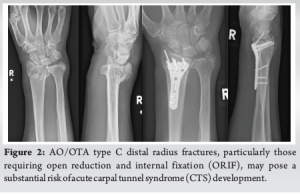

Distal radius fractures are the leading cause of ACTS. Earp et al. [8] identified open DRFs and also AO/OTA type C fractures as the main risk factors for developing the syndrome. Cooke et al. [9] reported a higher ACTS incidence in patients undergoing ORIF, likely due to high-energy trauma. Among the cases reviewed, three patients developed ACTS after surgical management of AO/OTA type C DRFs – one acute and two transient or subacute. The acute case occurred post-ORIF, suggesting a higher risk with this procedure. High-energy trauma, complete articular fractures, and open fractures appear to also increase ACTS incidence, likely due to post-operative swelling, hematoma, and biomechanical changes. This study highlights the need for vigilant monitoring and awareness of ACTS in such cases, notably in AO/OTA type C DRFs particularly those requiring an ORIF, as demonstrated by our study (Fig. 2). Finally, further research is needed to clarify the role of prophylactic carpal tunnel release, as its use in DRFs is debatable in medical literature.